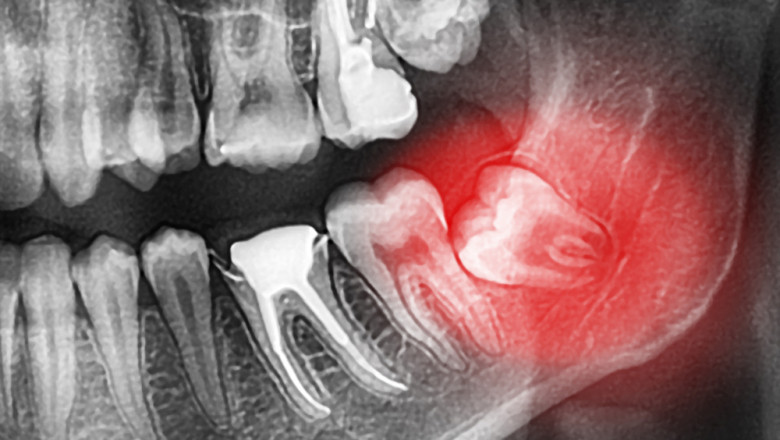

Dental Clinic Oral Surgery Sedation kwcdental 670 views Are you looking for oral surgery sedation? Visit https://www.kwcdental.com. At KWC Dental, for all surgical procedures, patients may discuss sedation options with a dentist. For more details, visit site. oral surgery sedation